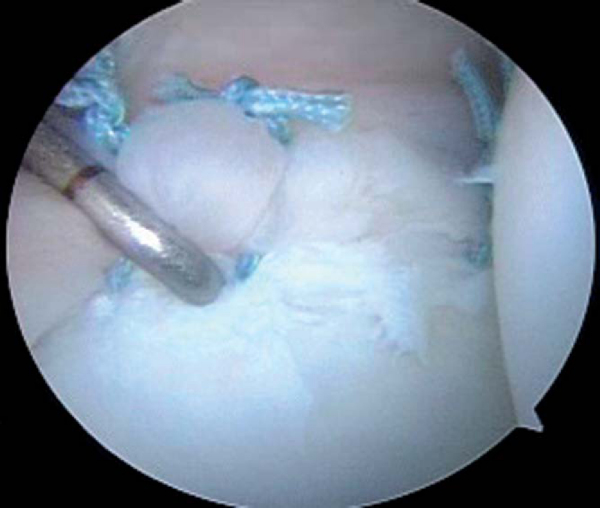

| • | The majority of patients with unidirectional posterior instability and primary posterior multidirectional instability do not have a posterior labral tear and typically display significant capsular laxity at arthroscopy ( Fig. 8-15 ). An isolated posterior capsulorrhaphy is performed. |

|

| • | Suture capsulorrhaphies are placed from inferior (6-o’clock) to superior (10-o’clock). | |

| • | The 6:30 capsular suture is typically advanced to the 7:30 position, and the reduction in capsular volume is assessed. | |

| • | Restoration of adequate tension in the posterior band of the inferior glenohumeral ligament is critical. | |

| • | Additional sutures are then placed at the 7:30, 8:30, and 9:30 positions on the capsule, advancing to the 8:30, 9:30, and 10:30 positions on the glenoid ( Fig. 8-16 ). |

| • | Sutures are tied after each is passed. If the sutures are not tied until the end, one errant suture may necessitate removal of all other sutures to achieve correction. |